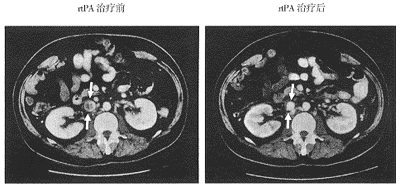

普通肝素和低分子肝素均产生令人满意的效果,至少在短期内可对比增强CT显示,(左图)重组组织型纤溶酶原激活物(rtPA)治疗前,肾静脉下方下腔静脉内存在大血栓(白色箭头)。(右图)治疗后1个月静脉持续通畅

图1 计算机断层摄影扫描